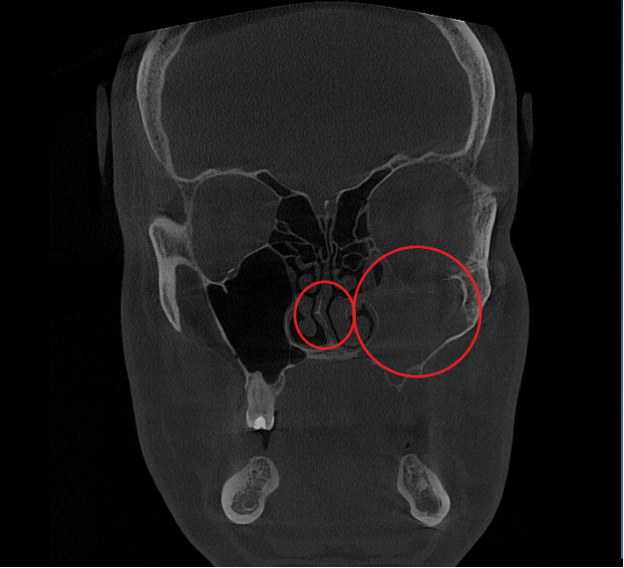

- Компьютерная томография (КЛКТ) околоносовых пазух и височных костей: Этот высокоинформативный метод диагностики объективно показал искривление носовой перегородки вправо, субтотальное снижение пневматизации (воздушности) левой верхнечелюстной пазухи, что свидетельствовало о хроническом воспалительном процессе. Костно-деструктивных изменений не выявлено.

- Хронический левосторонний верхнечелюстной синусит (J32.0). Длительное воспаление слизистой оболочки левой гайморовой пазухи, подтвержденное КТ.

Послеоперационный период протекал гладко. Проводились регулярные туалеты полости носа, промывание оперированной пазухи, назначались средства для увлажнения и регенерации слизистой оболочки, а также местная антибактериальная терапия. По результатам оперативного лечения носовое дыхание было полностью восстановлено, признаки активного воспаления купированы. Спустя 1.5 месяца после проведенного оперативного лечения проведено КТ околоносовых пазух в динамике, что отражает промежуточный результат оперативного лечения. На снимках: Перегородка носа располагается по центру, оперативно созданное соустье левой верхнечелюстной пазухи функционирует, пневматизация левой верхнечелюстной пазухи значительно улучшилась. Окончательный результат можно будет оценить через 3 месяца после проведенной операции, и при полной пневматизации левой верхнечелюстной пазухи пациент сможет приступить к установке зубных имплантов в верхнюю челюсть слева.